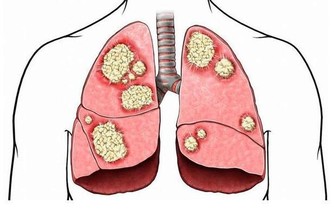

因為有了這一次治療頸椎和胸椎的經驗以後,發現很多患有頸椎病、腰椎病的人,在頸椎以下、腰椎以上相連接的椎體上,均存在著錯位,因此,得出一條重要結論:頸椎有病連著肺,腰椎有病連著胃。

這句話講的是什麼意思呢?頸七椎向下相連的是胸椎的一椎、二椎,這兩個椎體與肺相通,是通往肺的通路,當頸椎扭傷一定牽連到胸椎的一、二椎;腰椎向上相連的是胸十椎、十一椎、十二椎,十一椎、十二椎與脾、胃相通,是通往脾胃的通路,當腰椎扭傷一定牽連到胸十、十一椎。

胸一椎:上臂手腕指,食管氣管小魚際;心悸胸痛伴咳喘,肩臂疼痛難呼吸。

胸二椎:循腋至肘上;三至十二胸肋肌;咳嗽氣喘上臂痛,心悸心慌心胸疾。